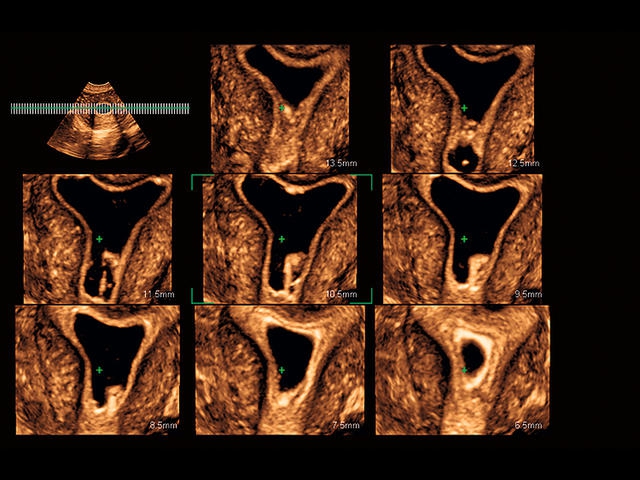

Обновленная версия легендарного УЗ-сканера. Стационарный аппарат экспертного класса Aplio 500 Toshiba NEW, визуализирует анатомические структуры в высоком разрешении. Модель позволяет выявить микрокальцификаты, новообразования, нарушения в работе сердца, сосудов и мышц. Присутствует функция виртуальной эндоскопии, 4D-сканирования, эластометрии тканей, УЗИ с контрастированием. За повышение качества изображения отвечают технологии ApliPure и Superb Microvascular Imaging. Первая задействует возможности пространственного и частотного кодирования, формирует цельный визуальный ряд с сохранением клинических маркеров. Вторая улучшает отображение микрососудистого русла, используя доплеровский эффект. Модель оснащена 21-дюймовым монитором, имеет 4 активных порта. Возможно подключение педиатрических, интраоперационных, лапароскопических и чреспищеводных датчиков.

• D-THI.Режим дифференцированной тканевой гармоники, повышающий качество визуализации глубоко расположенных тканей. Получаемое изображение отличается высокой четкостью, не содержит дефектов в виде «заснеженных» и размытых участков.